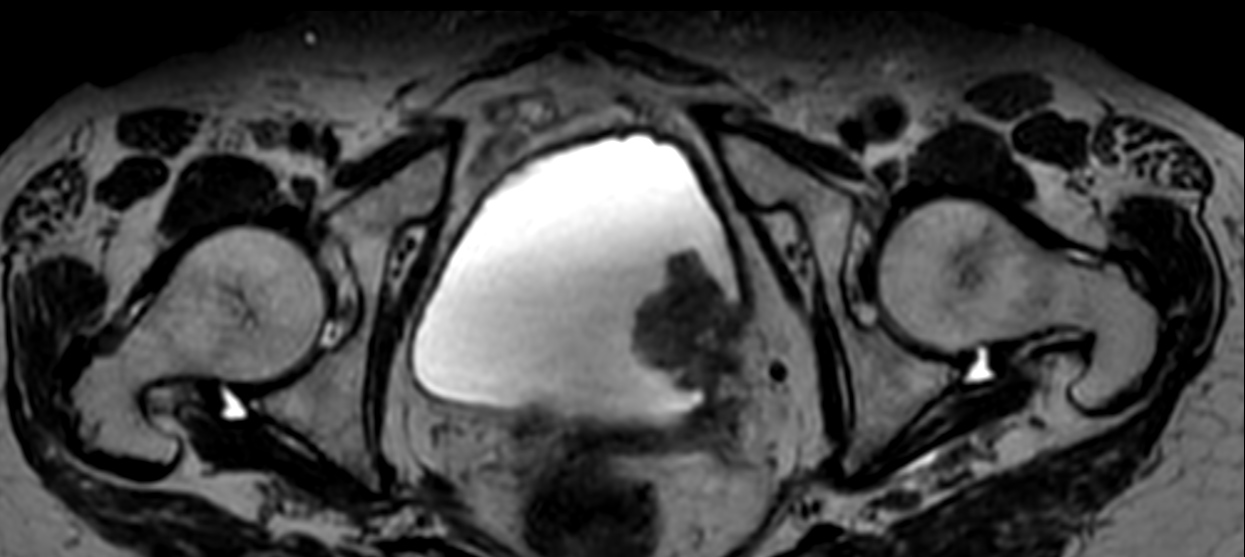

T1w TSE MultiVane XD

3D bTFE Compressed SENSE